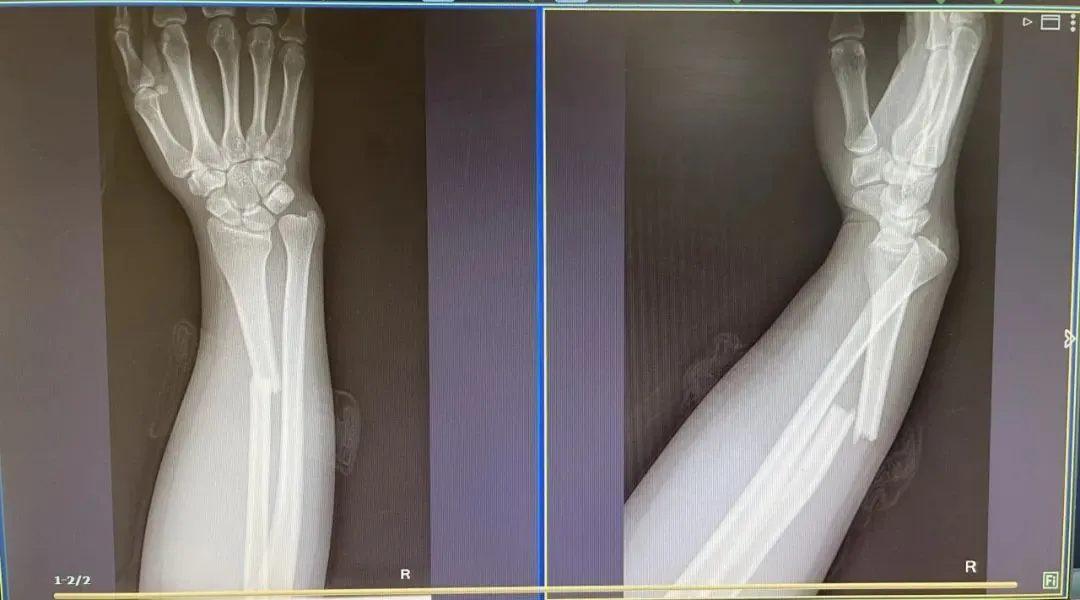

2019 年,36 岁的刘女士出游时,与孩子一同坐在行李箱上“滑行”,不料两人突然失去重心摔倒在地,孩子脸部擦伤,刘女士手臂也骨折了。

图源:广州广播电视台

医生表示,如果孩子不小心摔伤,且受伤部位出现疼痛、肿胀或明显畸形,无法正常活动,家长应高度怀疑骨折的可能。此时切勿随意移动,可用硬纸板托住患肢并抬高,减轻肿胀,迅速就医。国庆假期结束,返程高峰已至,请家长千万不要让孩子骑坐在行李箱上,一旦发现此类行为,应及时制止以免造成意外伤害。